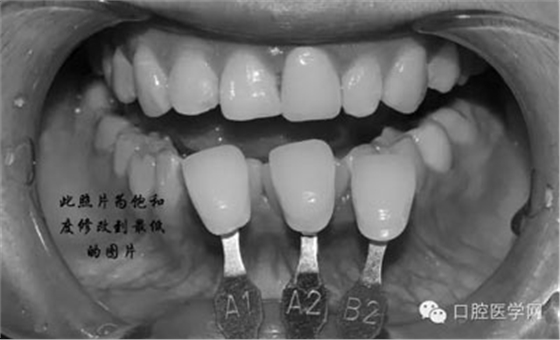

將比色照飽和度調(diào)到最低有助于牙齒明度的選擇

將比色照的飽和度調(diào)到最高有助于牙齒道飽和度選擇